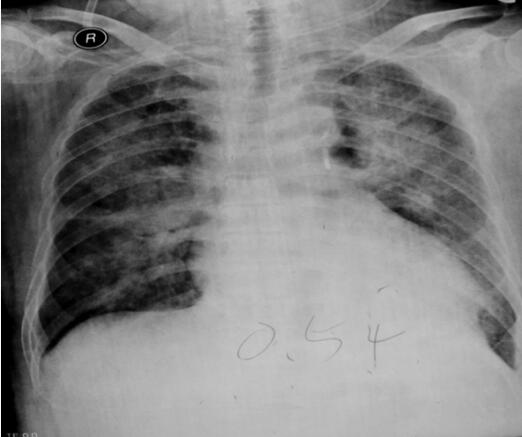

胸部X线示:肺淤血、间质性肺水肿,心脏增大,考虑心衰所致(图1-28-9)。

图1-28-9 入院时胸部X线片